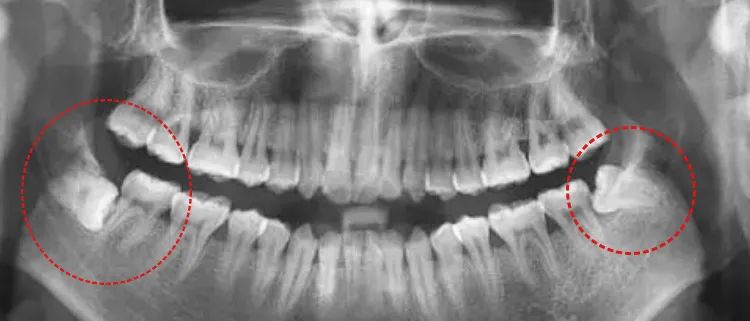

比如长得奇奇怪怪的智齿。判断智齿有无危害邻牙、确认离神经管的距离、判断其准确位置,方便更好处理。